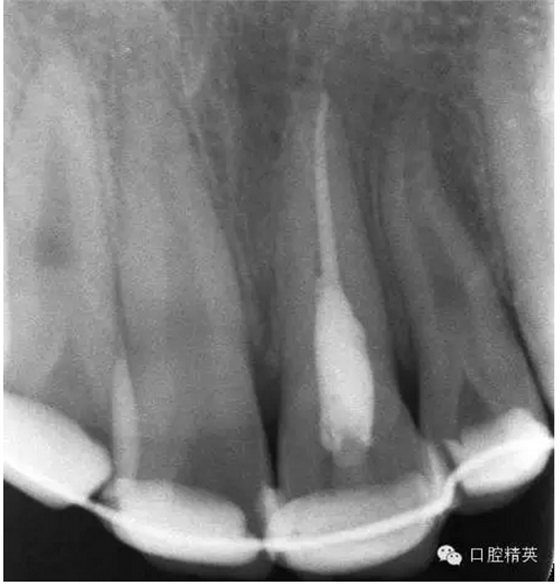

x線檢查:21牙槽窩空虛,窩內(nèi)未見(jiàn)其他遺留物。

圖3.患者21根尖片,牙槽窩空虛,無(wú)變形。

圖18.復(fù)位臨時(shí)固定后的x線根尖片?;颊哐栏c牙槽窩吻合。

圖23.樹(shù)脂+牙弓夾板固定完成后的x線片影像

圖5.拆除樹(shù)脂夾板前的x線根尖片影像,21根尖出現(xiàn)少許吸收。大家擔(dān)心的情況出現(xiàn)了。